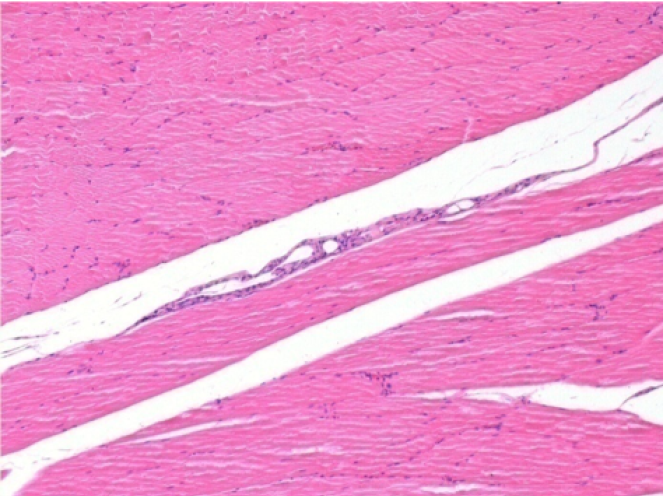

Через 3 місяці (90 днів) після ін'єкції Ендопіл 0,1 мл в правий претибіальний м'яз.